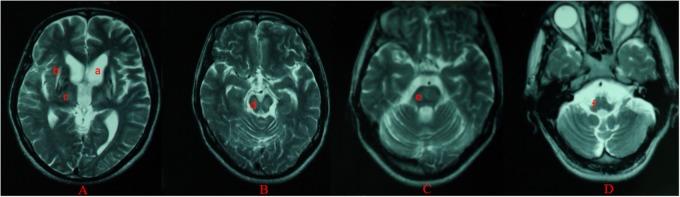

Wilson's disease (WD) is an inborn copper metabolism disease. Sex differences in clinical features of WD patients have been reported; however, the effect of sex on brain MRI is still unclear, especially for Chinese WD patients. Therefore, we aimed to examine sex differences in clinical correlates and brain MRI changes in WD patients in a Chinese Han population. 535 WD patients were enrolled and underwent MRI scanning. These patients were subdivided by the clinical symptoms, Kayser-Fleischer (K-F) rings, laboratory tests and sex. The mean age of onset and diagnosis, disease latency, localization of brain MRI lesions, and the level of copper metabolism were compared between male and female patients. The neuropsychiatric form (452 and 84.5%) was the most common subtype. Compared to female patients, male patients had a higher percentage in three clinical forms: neuropsychiatric form (263 and 58.2%), hepatic form (41 and 59.4%), and presymptomatic form (10 and 71.4%). In the neuropsychiatric form, male patients had the earlier age of onset and definitive diagnosis, and shorter time of disease latency than female patients. Putamen was the most common site for lesions in brain MRI of three groups. In the hepatic form, more male patients showed the ventricular widening than female patients (14/41 vs. 3/28; < 0.05). The level of serum ceruloplasmin and copper of WD patients with neuropsychiatric form was higher than that of male patients with hepatic or presymptomatic form. In women, however, patients of presymptomatic form have the highest level of the ceruloplasmin, and the level of serum copper in hepatic patients was highest. Our findings suggest sex differences in the percentage of three clinical forms. Meanwhile, the mean age of onset and diagnosis of female was higher than male, also happened in the disease latency. Only in the hepatic form, there was a sex difference in the ventricular widening.

威尔逊病(WD)是一种先天性铜代谢疾病。已有报道称WD患者的临床特征存在性别差异;然而,性别对脑部MRI的影响仍不明确,尤其是对于中国WD患者。因此,我们旨在研究中国汉族WD患者临床相关性和脑部MRI变化的性别差异。招募了535例WD患者并进行了MRI扫描。这些患者根据临床症状、凯泽-弗莱舍尔(K-F)环、实验室检查和性别进行了细分。比较了男性和女性患者的平均发病年龄和诊断年龄、疾病潜伏期、脑部MRI病变的定位以及铜代谢水平。神经精神型(452例,占84.5%)是最常见的亚型。与女性患者相比,男性患者在三种临床类型中的比例更高:神经精神型(263例,占58.2%)、肝型(41例,占59.4%)和症状前型(10例,占71.4%)。在神经精神型中,男性患者的发病年龄和确诊年龄更早,疾病潜伏期比女性患者短。壳核是三组脑部MRI中最常见的病变部位。在肝型中,男性患者出现脑室增宽的比例高于女性患者(14/41比3/28;<0.05)。神经精神型WD患者的血清铜蓝蛋白和铜水平高于肝型或症状前型男性患者。然而,在女性中,症状前型患者的铜蓝蛋白水平最高,肝型患者的血清铜水平最高。我们的研究结果表明三种临床类型的比例存在性别差异。同时,女性的平均发病年龄和诊断年龄高于男性,疾病潜伏期也是如此。仅在肝型中,脑室增宽存在性别差异。